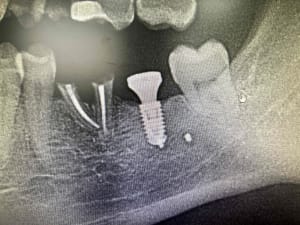

IMPLANT 36 DECORMIS MONIQUE.jpg